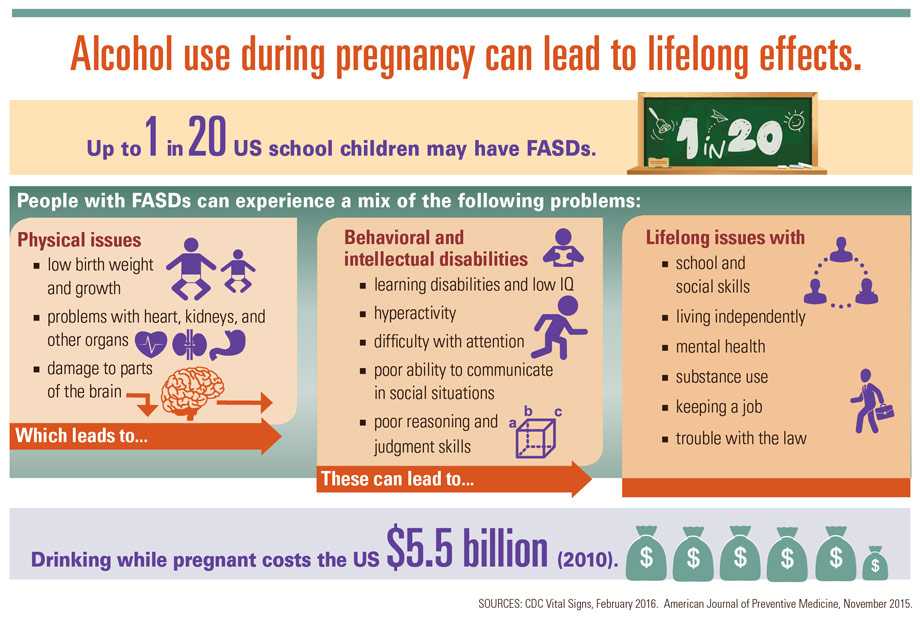

Alcohol use during pregnancy can cause fetal alcohol spectrum disorders (FASDs), which are physical, behavioral, and intellectual disabilities that last a lifetime. More than 3 million US women are at risk of exposing their developing baby to alcohol because they are drinking, having sex, and not using birth control to prevent pregnancy. About half of all US pregnancies are unplanned and, even if planned, most women do not know they are pregnant until they are 4-6 weeks into the pregnancy. This means a woman might be drinking and exposing her developing baby to alcohol without knowing it. Alcohol screening and counseling helps people who are drinking too much to drink less. It is recommended that women who are pregnant or might be pregnant not drink alcohol at all. FASDs do not occur if a developing baby is not exposed to alcohol before birth.

Alcohol can harm a developing baby before a woman knows she is pregnant.

- Women who are pregnant or who might be pregnant should be aware that any level of alcohol use could harm their baby.

- All types of alcohol can be harmful, including all wine and beer.

- The baby’s brain, body, and organs are developing throughout pregnancy and can be affected by alcohol at any time.

- Drinking while pregnant can also increase the risk of miscarriage, stillbirth, prematurity, and sudden infant death syndrome (SIDS).